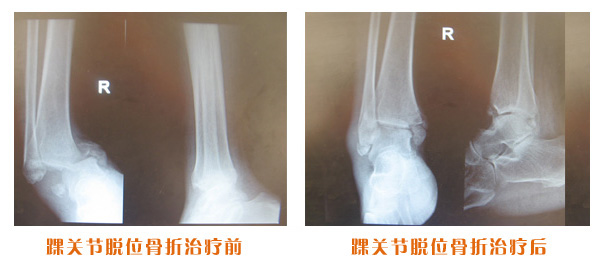

肥城市安駕莊梁氏骨科醫(yī)院是一所以梁氏手法正骨配合膏藥為特色的現(xiàn)代化??漆t(yī)院。

梁氏骨科術(shù)始創(chuàng)于清雍正年間,歷經(jīng)八代,至今已有三百年歷史。據(jù)1929年泰安縣志載“梁瑞圖先生,字增生,號(hào)蓮峰,安駕莊人,精岐黃并發(fā)明接骨,凡跌打車凡跌打車軋皮不破而碎骨者......【詳細(xì)】 |